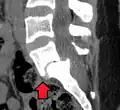

(A) Vista sagital de CT de un deslizamiento de bajo grado.

(B) Intervención preoperatoria de radiografía lateral.

(C) Tratado quirúrgicamente con descompresión L5 – S1, fusión instrumentada y colocación de un injerto intersomático entre L5 y S1.